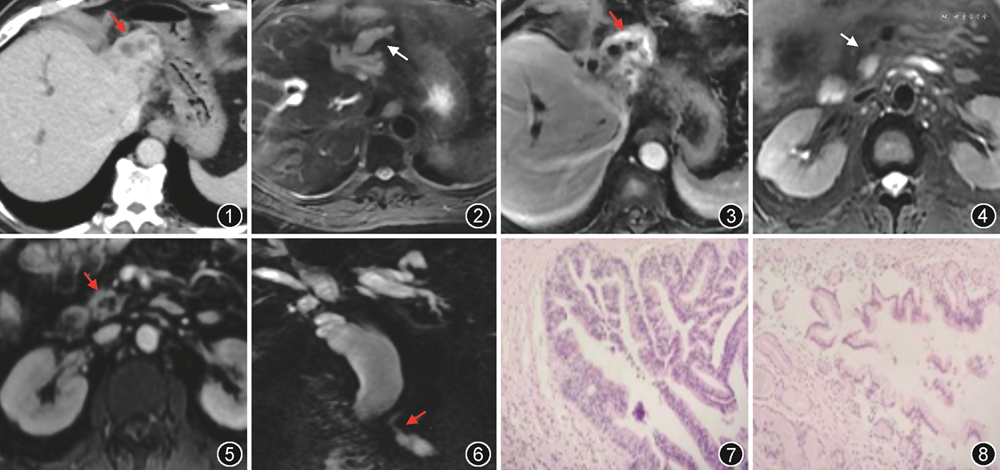

上腹部CT示肝左叶实质萎缩,肝内胆管扩张,左叶为著,最宽处直径约2 cm,肝左叶外侧段胆管壁不规则增厚伴轻中度延迟强化,延迟期见多个强化小结节呈锯齿状突入胆管腔内(图1);肝总管、胆总管明显扩张,最宽处直径约2.3 cm;胰腺钩突部见椭圆形低密度影,大小1.6 cm×1.5 cm,边界清晰,平扫CT值为20 HU,增强后见囊壁及分隔延迟强化。上腹部MRI示肝左叶扩张的胆管壁不规则增厚,增强后见胆管腔内延迟强化小结节影(图2,3);胰腺钩突部见异常信号灶,T1WI呈低信号,T2WI呈高信号(图4),边界清晰,增强后见囊壁和分隔延迟强化(图5)。MR胰胆管成像(MR cholangiopancreatography,MRCP)示肝内胆管、左右肝管及胆总管明显扩张,胰腺钩突部病灶与主胰管相通,主胰管轻度扩张(图6)。

患者行肝左叶切除术和胰十二指肠切除术。肝脏剖面见肝内胆管扩张,胆管内壁粗糙,局部可见小突起。镜下见囊壁样组织,被覆单层柱状上皮,局部乳头状突起,细胞核呈轻-中度异型性,胞质含黏液,局部黏液消失伴腺体融合,局灶可见异型细胞浸润导管周围间质。免疫组化结果:CDX-2(+)、MUC2(+)、CD34(血管+)和D2(血管+)。病理诊断为左半肝-肝内胆管乳头状黏液性肿瘤(intraductal papillary mucinous neoplasm of the biliary tract,IPMN-B)癌变伴局灶浸润,呈高-中分化导管腺癌(图7)。胰腺病变区见管腔扩张,内壁灰白色、光滑,镜下见黏液柱状上皮增生,呈乳头状排列,上皮低级别异型增生,病理诊断为胰腺导管内乳头状黏液性肿瘤(intraductal papillary mucinous neoplasm of the pancreas,IPMN-P)伴上皮轻度异型(图8)。